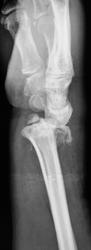

Травма. Пациент направлен на рентгенографию лучезапястного сустава.

перелом луча с отрывом шиловидного отростка. Вывих в лучезапястном суставе. Видимо упал с лестницы или неудачное голосование?

Истинный тыльный вывих кисти. Внутрисуставной оскольчатый перелом лучевой в типичном месте, перелом шиловидного отростка локтевой со смещением. А контроль после репозиции будет?